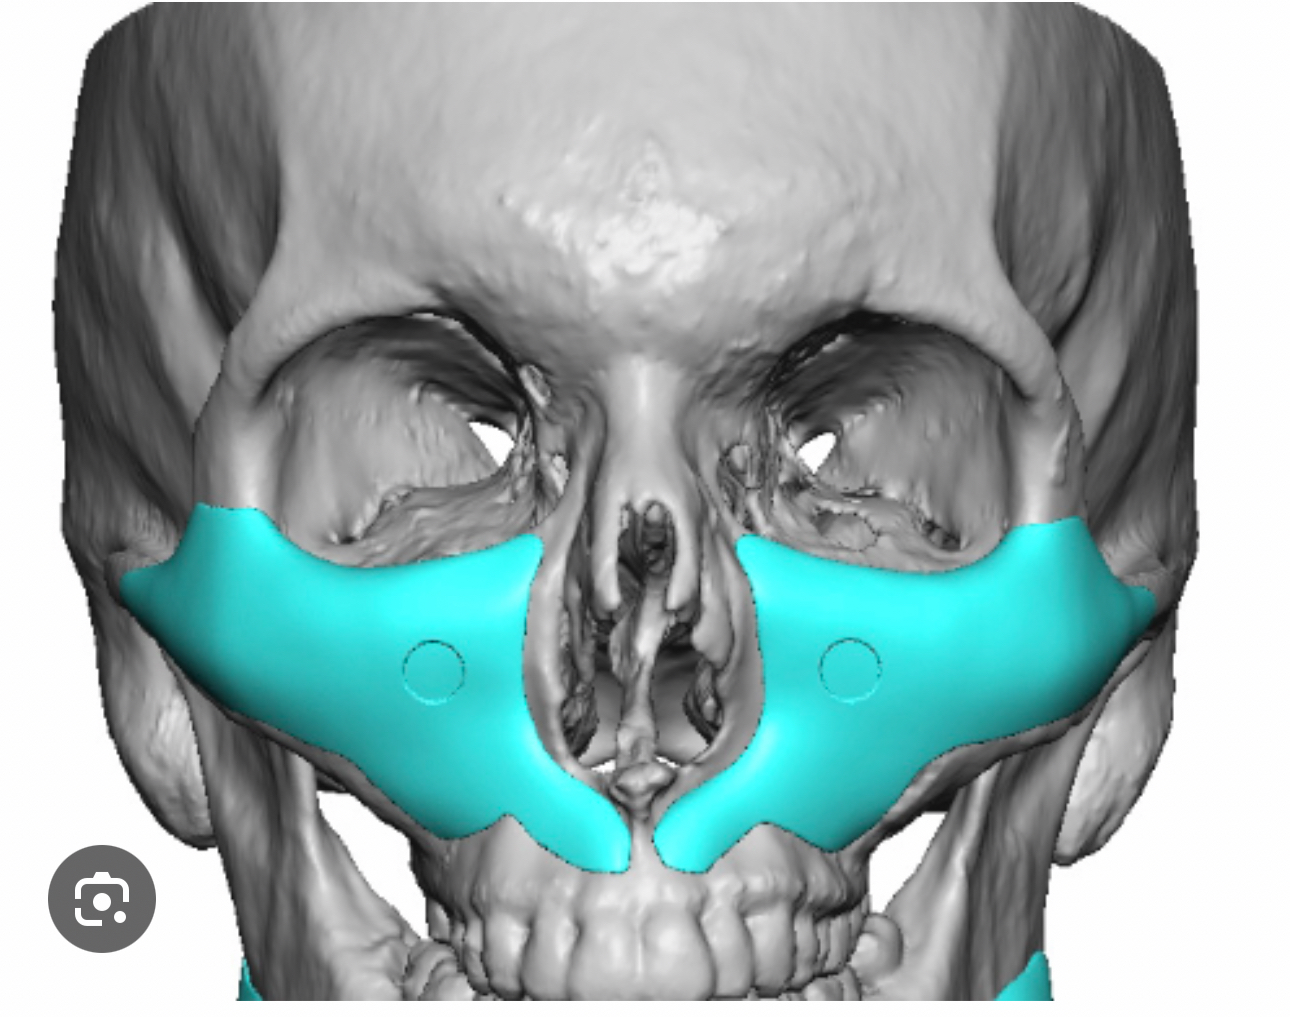

paranasals

as you can see now that some swellings gone down my nasolabials are getting more prominent again. I don't want fat grafting, i wanted to fake some bone support instead. Surgeon thinks a facelift oughtta do it, but id rather augment the structure, facelift seems like a subscription based service where ive gotta do it again and again over the years to keep fixing it.

I've seen a few different shapes, ones with a hood on each side of the nose, ones with one big hoof under the nose, and ones that trace all the way up the side if the nose and also augment the infras. This is more of a full midface augmentation. Do these look stupid in practice or no?

Should I get paranasals, and what shape would work best?

as you can see now that some swellings gone down my nasolabials are getting more prominent again. I don't want fat grafting, i wanted to fake some bone support instead. Surgeon thinks a facelift oughtta do it, but id rather augment the structure, facelift seems like a subscription based service where ive gotta do it again and again over the years to keep fixing it.

I've seen a few different shapes, ones with a hood on each side of the nose, ones with one big hoof under the nose, and ones that trace all the way up the side if the nose and also augment the infras. This is more of a full midface augmentation. Do these look stupid in practice or no?

Should I get paranasals, and what shape would work best?